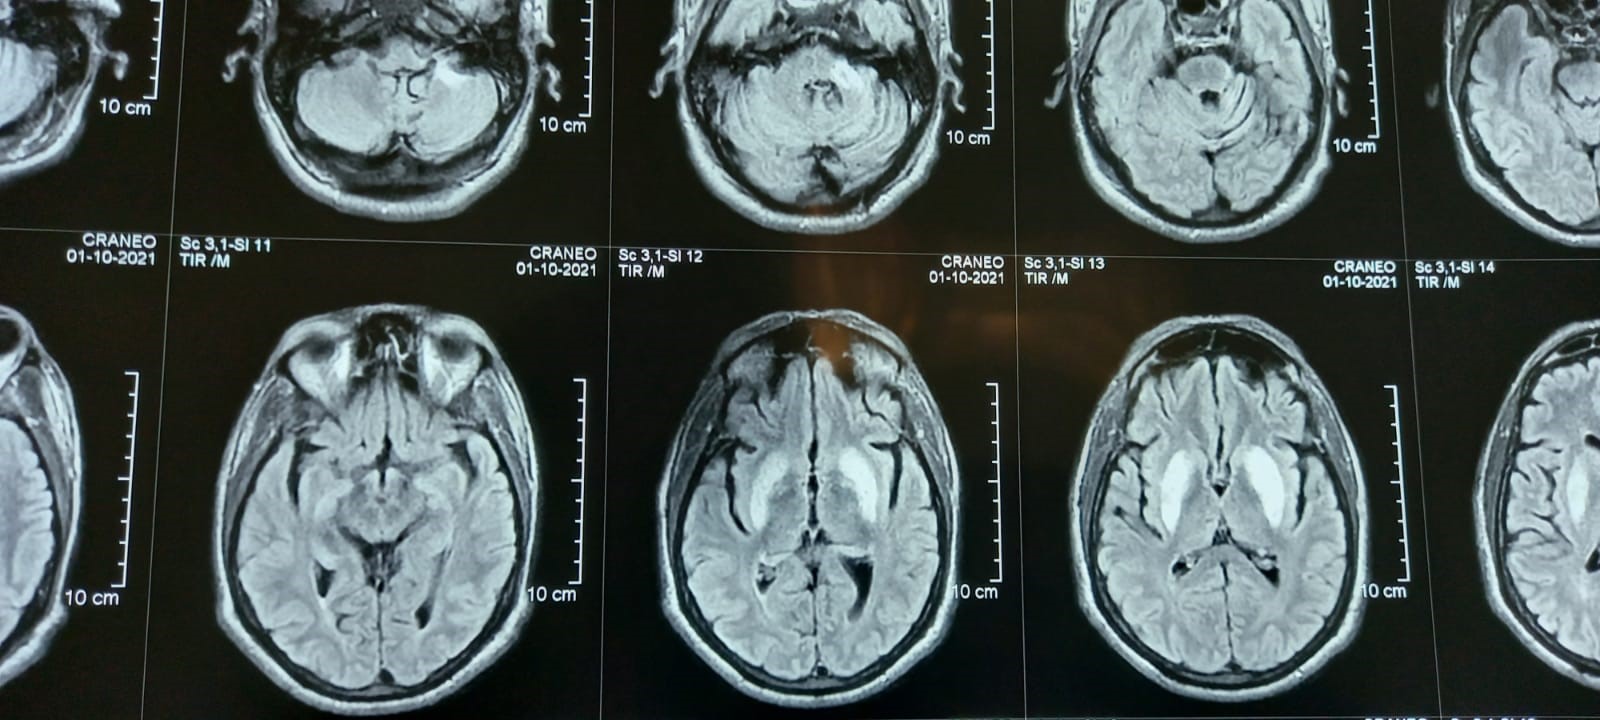

Method: An emergency department evaluation the blood urea nitrogen of 67 mg/dL, and serum creatinine of 9.6 mg/dL; Sodium: 137 mmol/L, Calcium: 8.6 mg/dL, Phosphorus: 3.9 mg/dL, Magnesium: 1.85 mg/dL, Potassium: 5.00 mmol/L, Iron: 61, TIBC: 161, Ferritin: 2374, Intact PTH: 387 (pg/mL). He was medicated with haloperidol at the emergency room, and hospitalization to optimize hemodialysis therapy. A magnetic resonance imaging (MRI) brain was obtained showing basal ganglia hyperintensity in T2W and FLAIR images. (Figure 1).

Figure 1. MRI